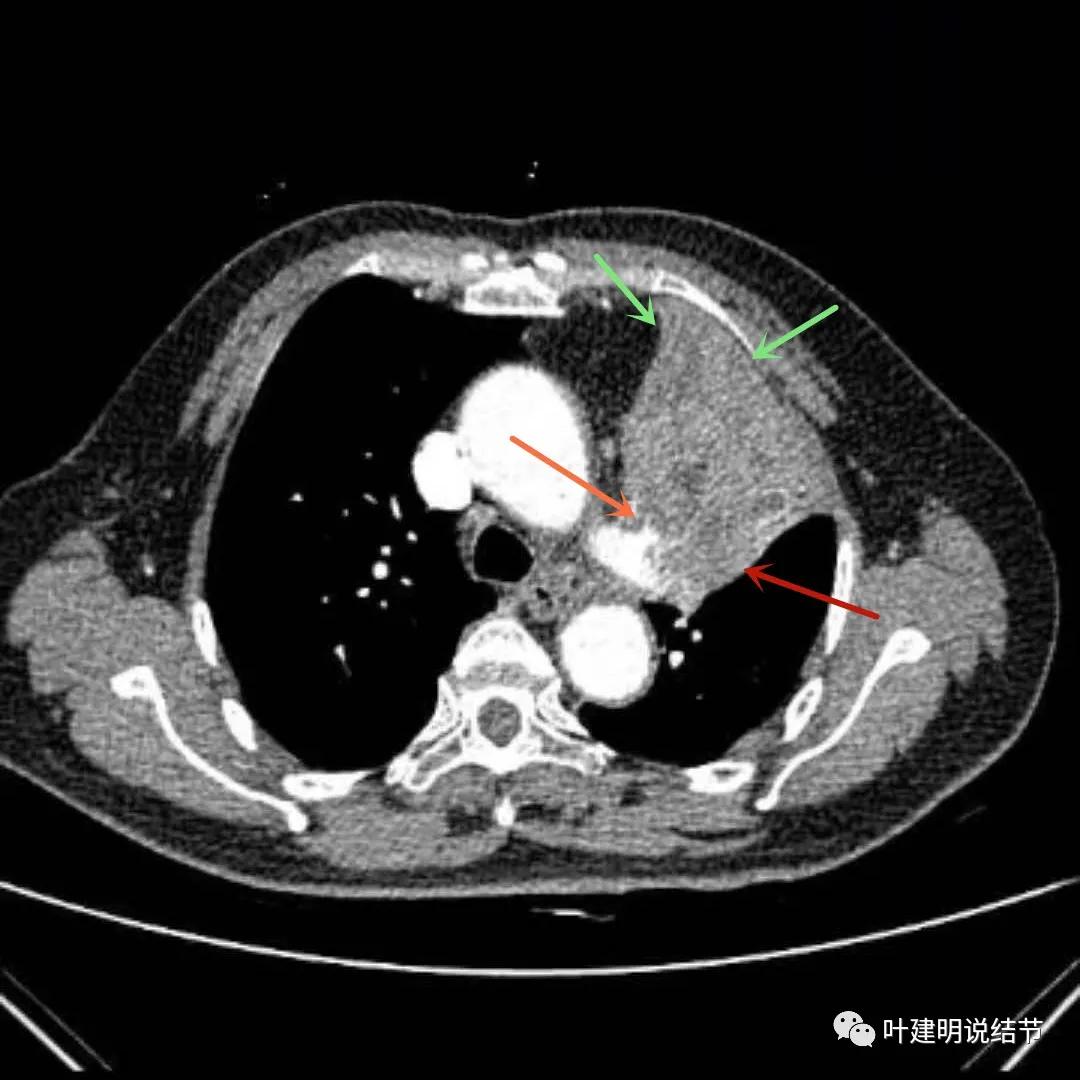

上图绿色箭头所指区域考虑为肺不张,红色示肿瘤处且有不均质与膨胀性,桔色细箭头所指处是被肿瘤包绕的肺动脉分支起始部,粗桔色箭头示肺动脉与肿瘤间紧密愈着,考虑有侵犯肺动脉

上图绿色箭头所指区域考虑为肺不张,红色示肿瘤处,黄色箭头示肿瘤区域内有坏死低密度,桔色细箭头所指处是被肿瘤包绕的肺动脉分支起始部,粗桔色箭头示肺动脉与肿瘤间紧密愈着,考虑有侵犯肺动脉